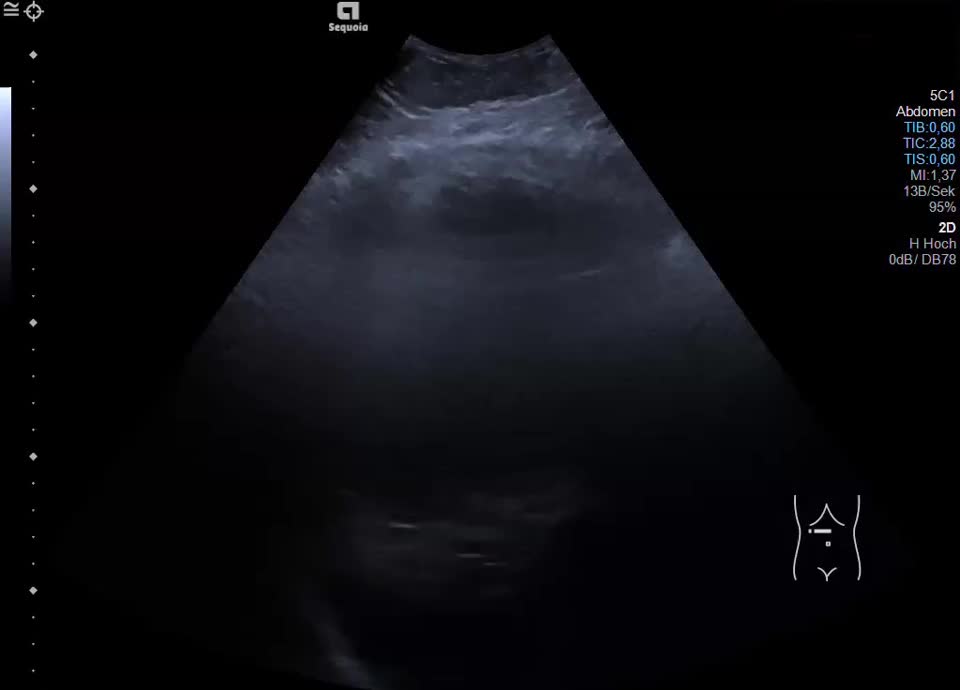

Hepatic hematoma

Intrahepatisches Hämatom und hämorrhagischer Aszites bei Zustand nach Punktion